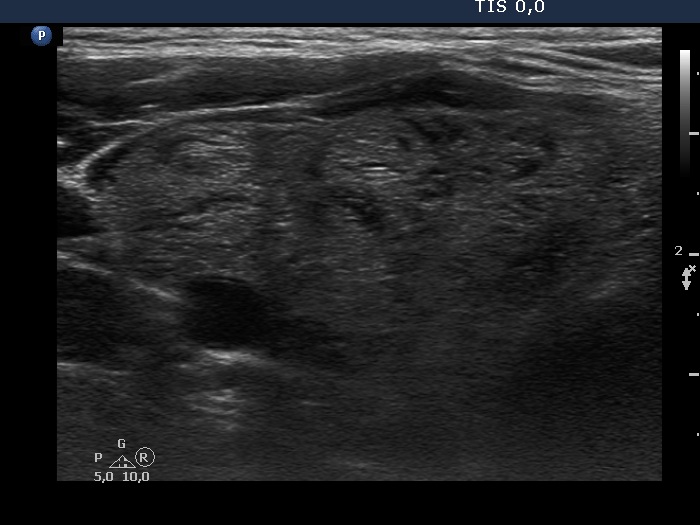

Ultrasonography. The thyroid was greatly enlarged and was composed of numerous nodules. The non-nodular part appeared as echonormal islets within the thyroid. The nodules varied in echogenicity which ranged from moderately hypoechogenic to hyperechogenic. Most nodules had cystic areas, as well. There was no nodule of oncological significance.